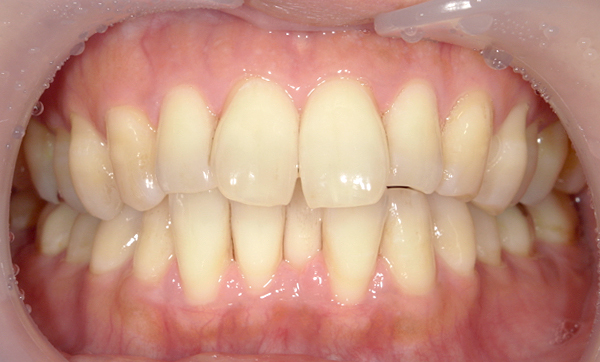

症例:上下顎の部分矯正

症例_009 前歯「八の字/V字型」症例

治療期間:11ヶ月金額:60万円+税40代女性八の字/V字型前歯のガタガタ捻転歯